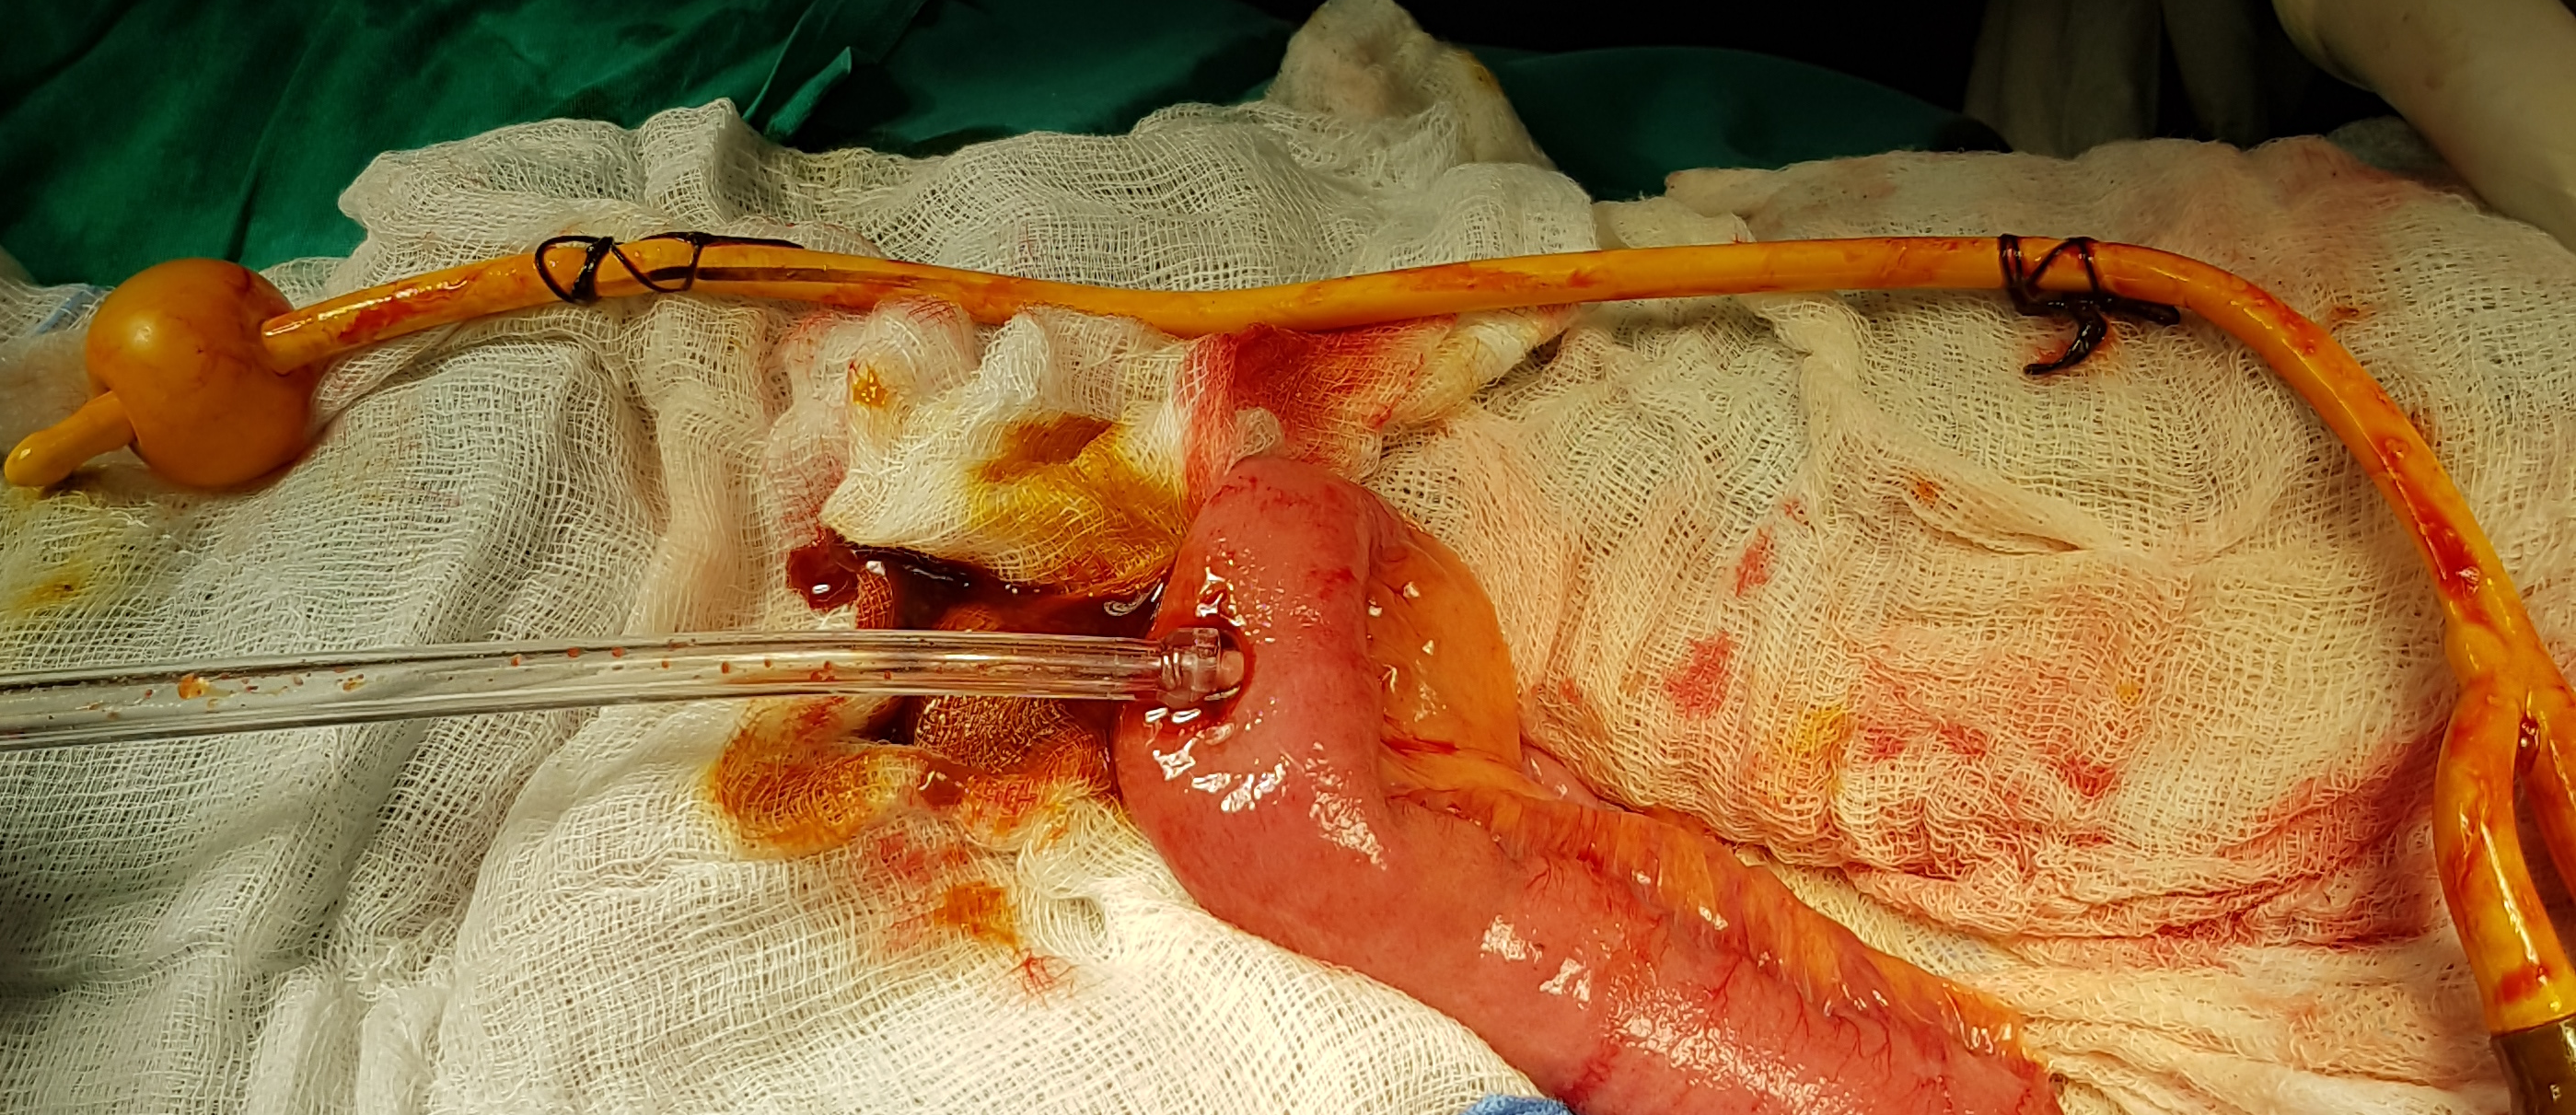

Closed systems for hyperthermic intraperitoneal chemotherapy (Courtesy Dr. V. Penopoulos)